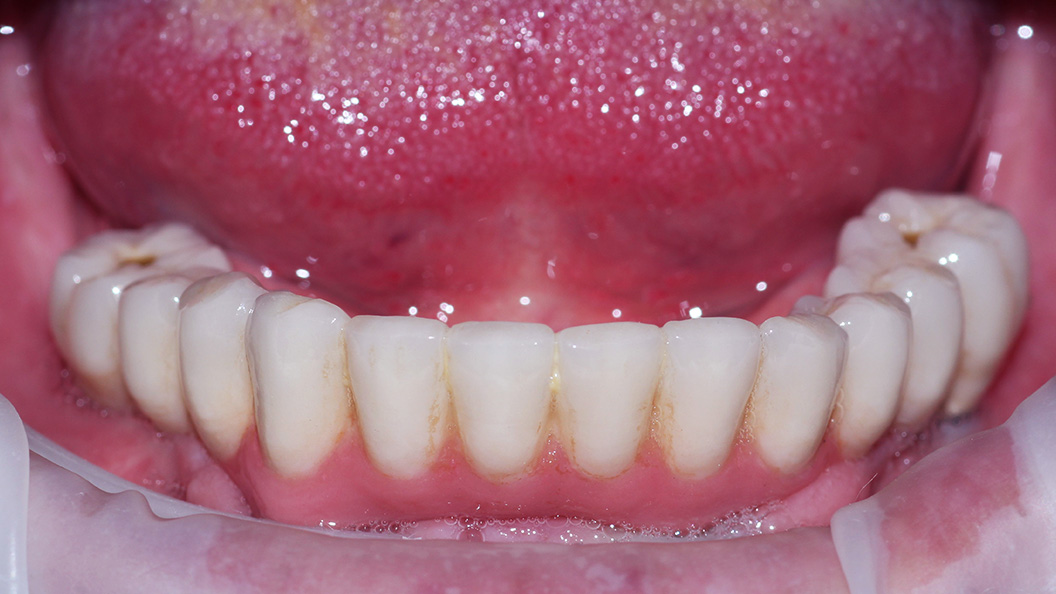

До и после лечения

В нашу клинику обратился пациент с жалобами на полное отсутствие зубов на нижней челюсти.

Осмотр проводил врач стоматолог-ортопед и хирург Мельников Алексей Владимирович. После консультации, совместно с пациентом, было решено провести протезирование по технологии All-on-4.

Методика позволяет восстановить зубной ряд на 4-х имплантах, установленных по определённой технологии. Протез при этом фиксируется сразу после имплантации.

В ходе процедуры были проведены следующие работы:

- профессиональная гигиена полости рта;

- изготовление протеза на основе предварительно созданной модели;

- вживление имплантов;

- фиксация протеза.